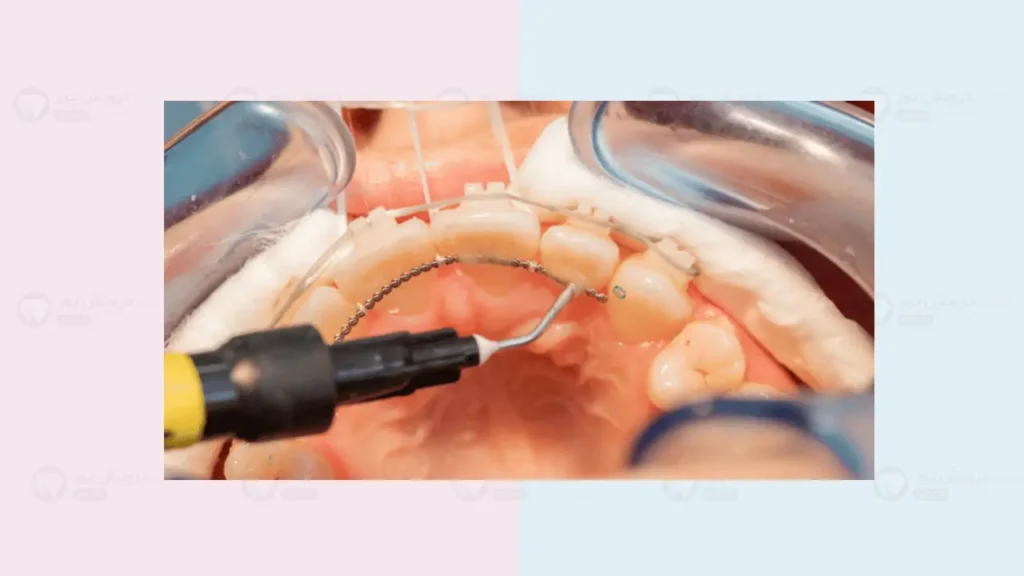

بعد از اینکه درمان ارتودنسی تمام شد، دکتر به شما می گوید که باید از نگهدارنده یا ریتینر ارتودنسی استفاده کنید. ریتینرها یا ثابت هستند یا متحرک ولی اغلب ریتینرهای ثابت پرطرفدار تر هستند چون پشت دندان قرار دارند و در برابر بازگشت دندان ها به حالت قبل عملکرد بهتری دارند. در این مقاله می خواهیم ببینیم که مدت زمان استفاده از ریتینر ثابت چقدر است؟ یعنی چند ماه یا چند سال باید از آن ها استفاده کرد. ما قبل از اینکه به این سوال پاسخ دهیم باید بفهمیم اصلا چرا باید از ریتینر استفاده کنیم؟

اگر سیم پشت دندان شکست یا کنده شد چه کار کنیم؟

حتی اگر چند ماه یا چند سال از ارتودنسی تان گذشتهباشد، شکستن این سیم یک زنگ خطر است. دندان ها مترصد فرصت هستند تا حرکت کنند. اگر متوجه شدید چسب یکی از دندان ها کندهشده(یا سیم مشکل دارد) یا زبان تان را اذیت می کند:

- اول اینکه دستکاری نکنید: سعی نکنید با ناخنگیر یا ابزار دیگر سیم را ببرید.

- زمان را از دست ندهید: در اولین فرصت (ظرف چند روز) به مطب دکتر ارتودنسی تان زنگ بزنید. اگر دکتر خودتان در دسترس نیست، هر متخصص ارتودنسی دیگری می تواند آن را برایتان تعمیر کند.

- پلاک متحرک را استفاده کنید: اگر پلاک متحرک هم دارید، تا زمان تعمیر سیم، حتماً شب ها از آن استفاده کنید تا دندان ها فرصت حرکت پیدا نکنند.